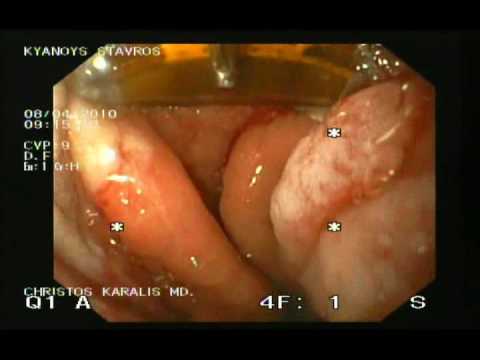

Przełyk Barretta - Endoskopowa Terapia Metodą...

Ablacja radiowa metodą Halo 90 i Halo 360 stanowi sposób leczenie takich stanów przedrakowych jak przełyk Barrett'a. Dużą jej zaletą jest mała ilość powikłań w postaci zwężeń wynosząca 6%. Materiał wideo...